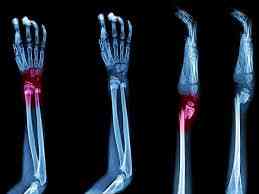

Symptoms of bone fracture

Symptoms of bone fractures include:

• Pain.

• Swelling.

• Tenderness.

• Inability to move a part of your body like you usually can.

• Bruising or discoloration.

• A deformity or bump that’s not usually on your body.